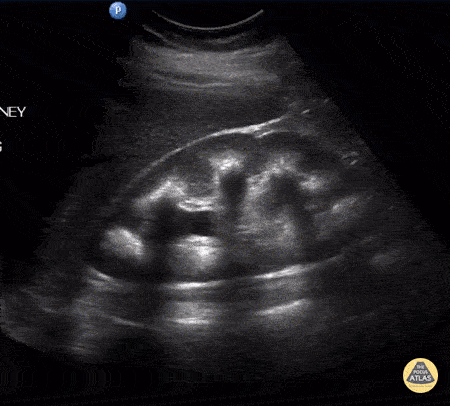

Renal/GU - Medullary Nephrocalcinosis with Moderate Hydronephrosis

A female patient presented with right flank pain. A longitudinal view of the right kidney indicates medullary nephrocalcinosis with posterior shadowing and moderate hydronephrosis. Note the posterior shadowing partially masks the hydronephrosis. Further ultrasound found a distal ureteral stone. Image courtesy of Robert Jones DO, FACEP @RJonesSonoEM Director, Emergency Ultrasound; MetroHealth Medical Center; Professor, Case Western Reserve Medical School, Cleveland, OH View his original post here